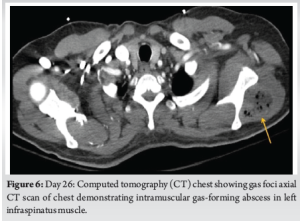

Radiographs of the knee revealed distal thigh subcutaneous and intramuscular emphysema (Fig. 3). MRI of the knee revealed a knee effusion, distal thigh fluid collections, and significant gas foci (Fig. 4). CT of the thigh also exhibited large multiseptated fluid collections in the anterior compartment of the thigh, gas to the level of the greater trochanter along fascial planes, a knee effusion, and diffuse soft-tissue edema (Fig. 5). LRINEC score was 9 [11-13]. The patient also complained of new-onset discomfort in the left shoulder and right posterior chest. A chest CT-scan revealed a gas-forming intramuscular abscess in his left infraspinatus muscle and a right posterior chest wall abscess without gas (Fig. 6).